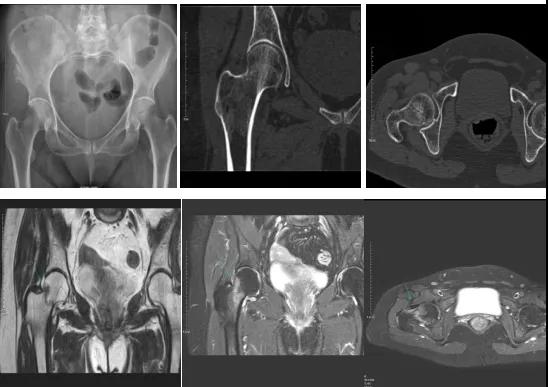

2.CT或MRI檢查。CT是斷面成像,不會(huì)出現(xiàn)重疊而導(dǎo)致漏診,同時(shí)CT還可以進(jìn)行多平面的重建,除了發(fā)現(xiàn)X線無法發(fā)現(xiàn)的骨折外,還可以三維直觀的顯示骨折的程度,對臨床治療有指導(dǎo)意義。CT無法發(fā)現(xiàn)骨裂、不全骨折或者骨挫傷,對軟組織的損傷診斷也有局限性,MRI就可以發(fā)現(xiàn)這些損傷。

DR示:右側(cè)股骨頸未見明顯骨折征象。CT右側(cè)股骨頸骨質(zhì)密度不均。患者體征明顯,為明確診斷,行MRI檢查。MRI示:右側(cè)股骨頸T1WI呈低信號(hào),脂肪抑制序列呈高信號(hào);提示右側(cè)股骨頸隱匿性骨折。